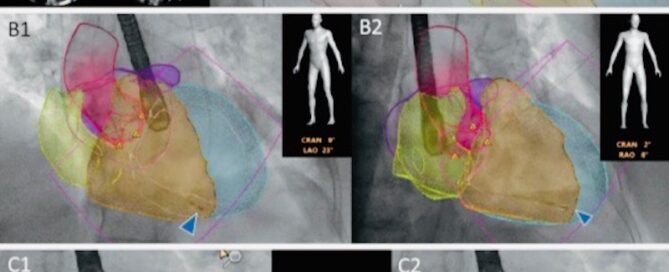

3D model with fluoroscopy (heart imaging)

Automated anatomical intelligence: next-generation fusion imaging for structural heart [...]